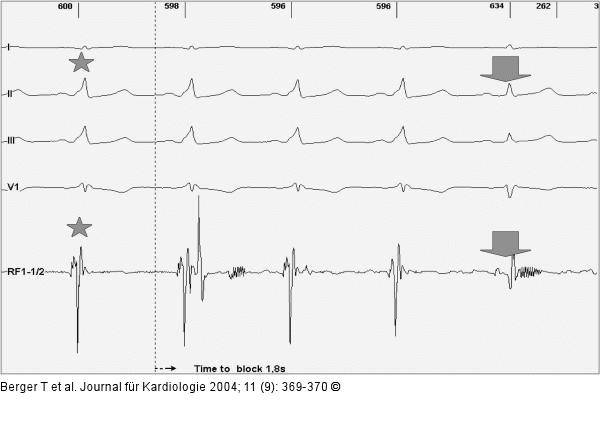

Abbildung 2: Paroxysmale Tachyarrhythmie |